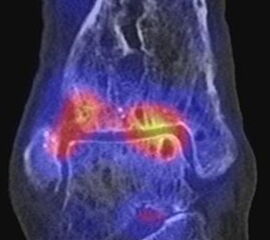

Die Abbildungen 4.2.a bis d zeigen den typischen Aspekt einer talacalcanearen Coalitio. Es besteht nur eine linksseitige, symptomatische Coalitio talocalcaneare (4.2.a und c); das 35 Tage zuvor angefertigte MRT zeigt keine auffälligen Signalveränderungen (4.2.b und d).

Abbildung 4.3. zeigt die Ursache für rechtsseitige Sprunggelenksbeschwerden bei einem Patienten mit talocalcanearen Coalitionen: nur die osteochondrale Läsion an der distalen rechten Tibia ist die Ursache des Schmerzes. Die bilateralen talocalcanearen Coalitionen sind asymptomatisch.